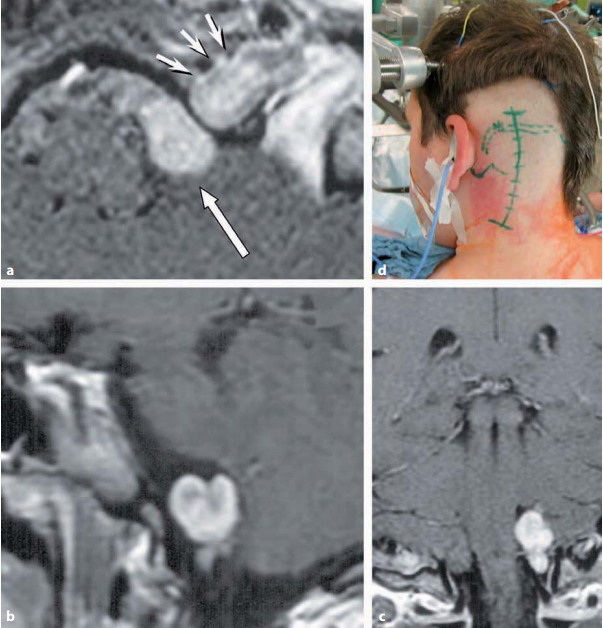

手术切除仍然是肿瘤根除的优选治疗方法。可以使用各种手术方法来切除听性肿瘤。在德国,听神经瘤手术切除中,神经外科医生大多首先选择乙状窦后入路,下文中会详细叙述。Nell...